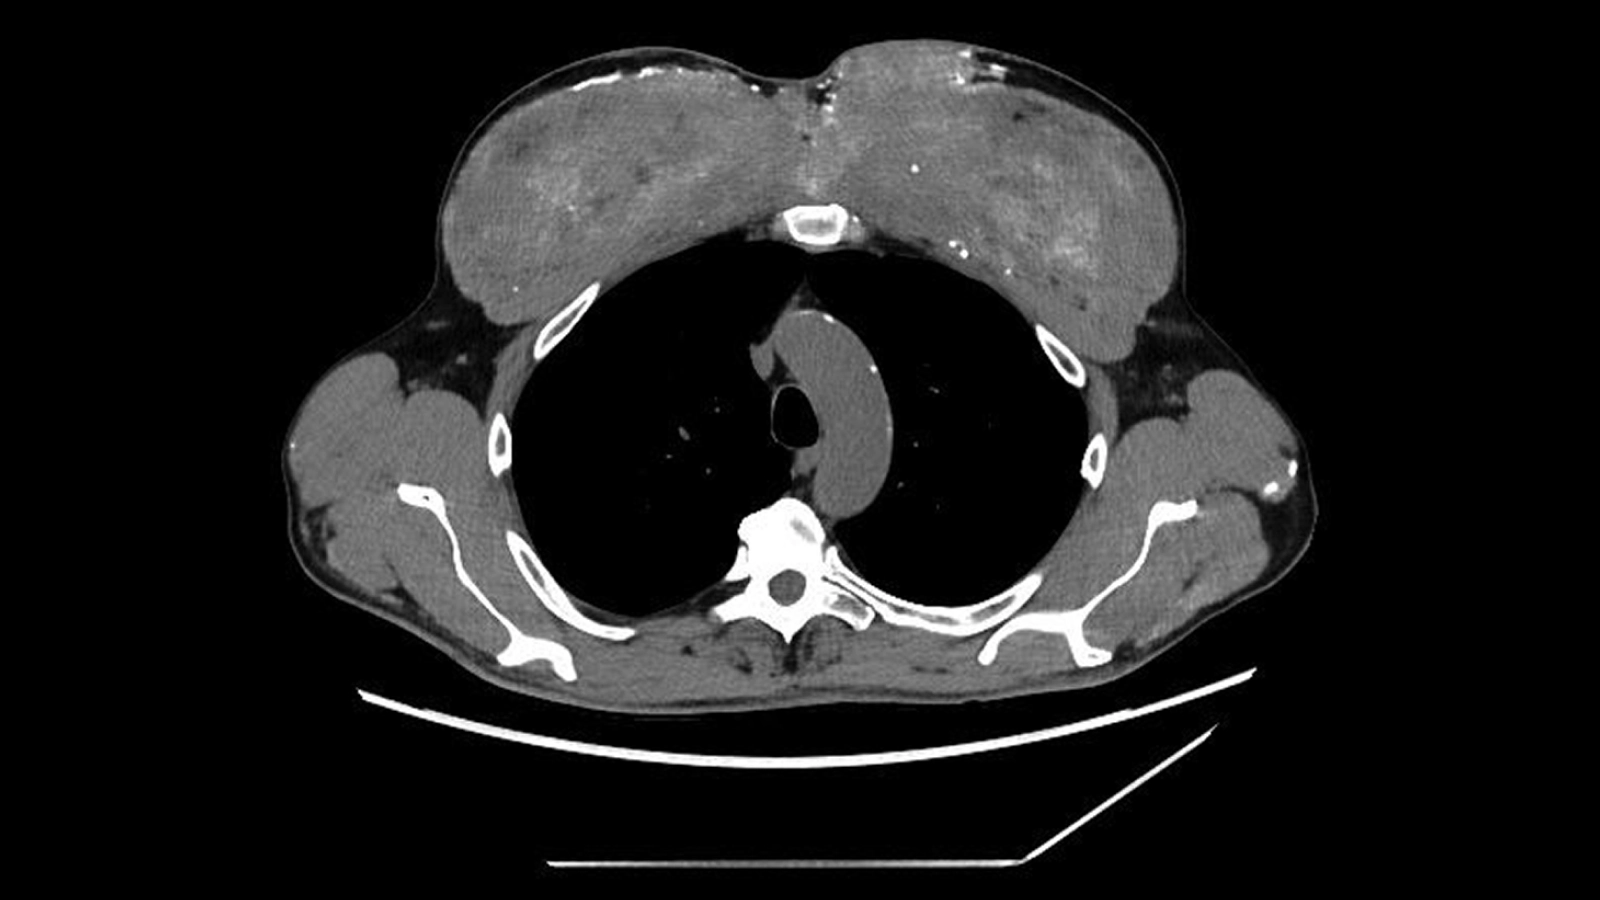

What happened next: Blood tests revealed that the man had elevated creatine and urea levels, indicating his kidneys were failing. His blood calcium levels were also dangerously high. CT scans then showed calcium deposits in his kidneys, pancreas and stomach, as well as scar-like areas in the back and lower parts of his lungs. These scans also showed unusual changes in his chest muscles; they appeared densely calcified.

The man was generally stable, but a physical exam showed noticeable changes in his upper-arm and chest muscles, matching the irregularities seen on the scans. The doctors then revisited the patient's medical history, and he shared a crucial detail: starting about 30 years earlier, he had started receiving "unknown intramuscular injections (probably containing testosterone)" into his chest and upper-arm muscles to enlarge them, according to a report of his case.

The diagnosis: Under the microscope, the muscle was filled with a silicone-like, oil-based substance and surrounded by dense calcium deposits. The team deduced that the man's past muscular injections probably contained synthol, a substance made primarily of oil that visually "plumps" up muscles, essentially inflating them like water balloons.

In this case, the synthol had triggered a persistent foreign-body reaction — the body essentially responding to material it could not break down. Over time, this reaction produced scarring and calcification, storing large amounts of calcium inside the muscle. And eventually, that calcium made its way into his bloodstream.